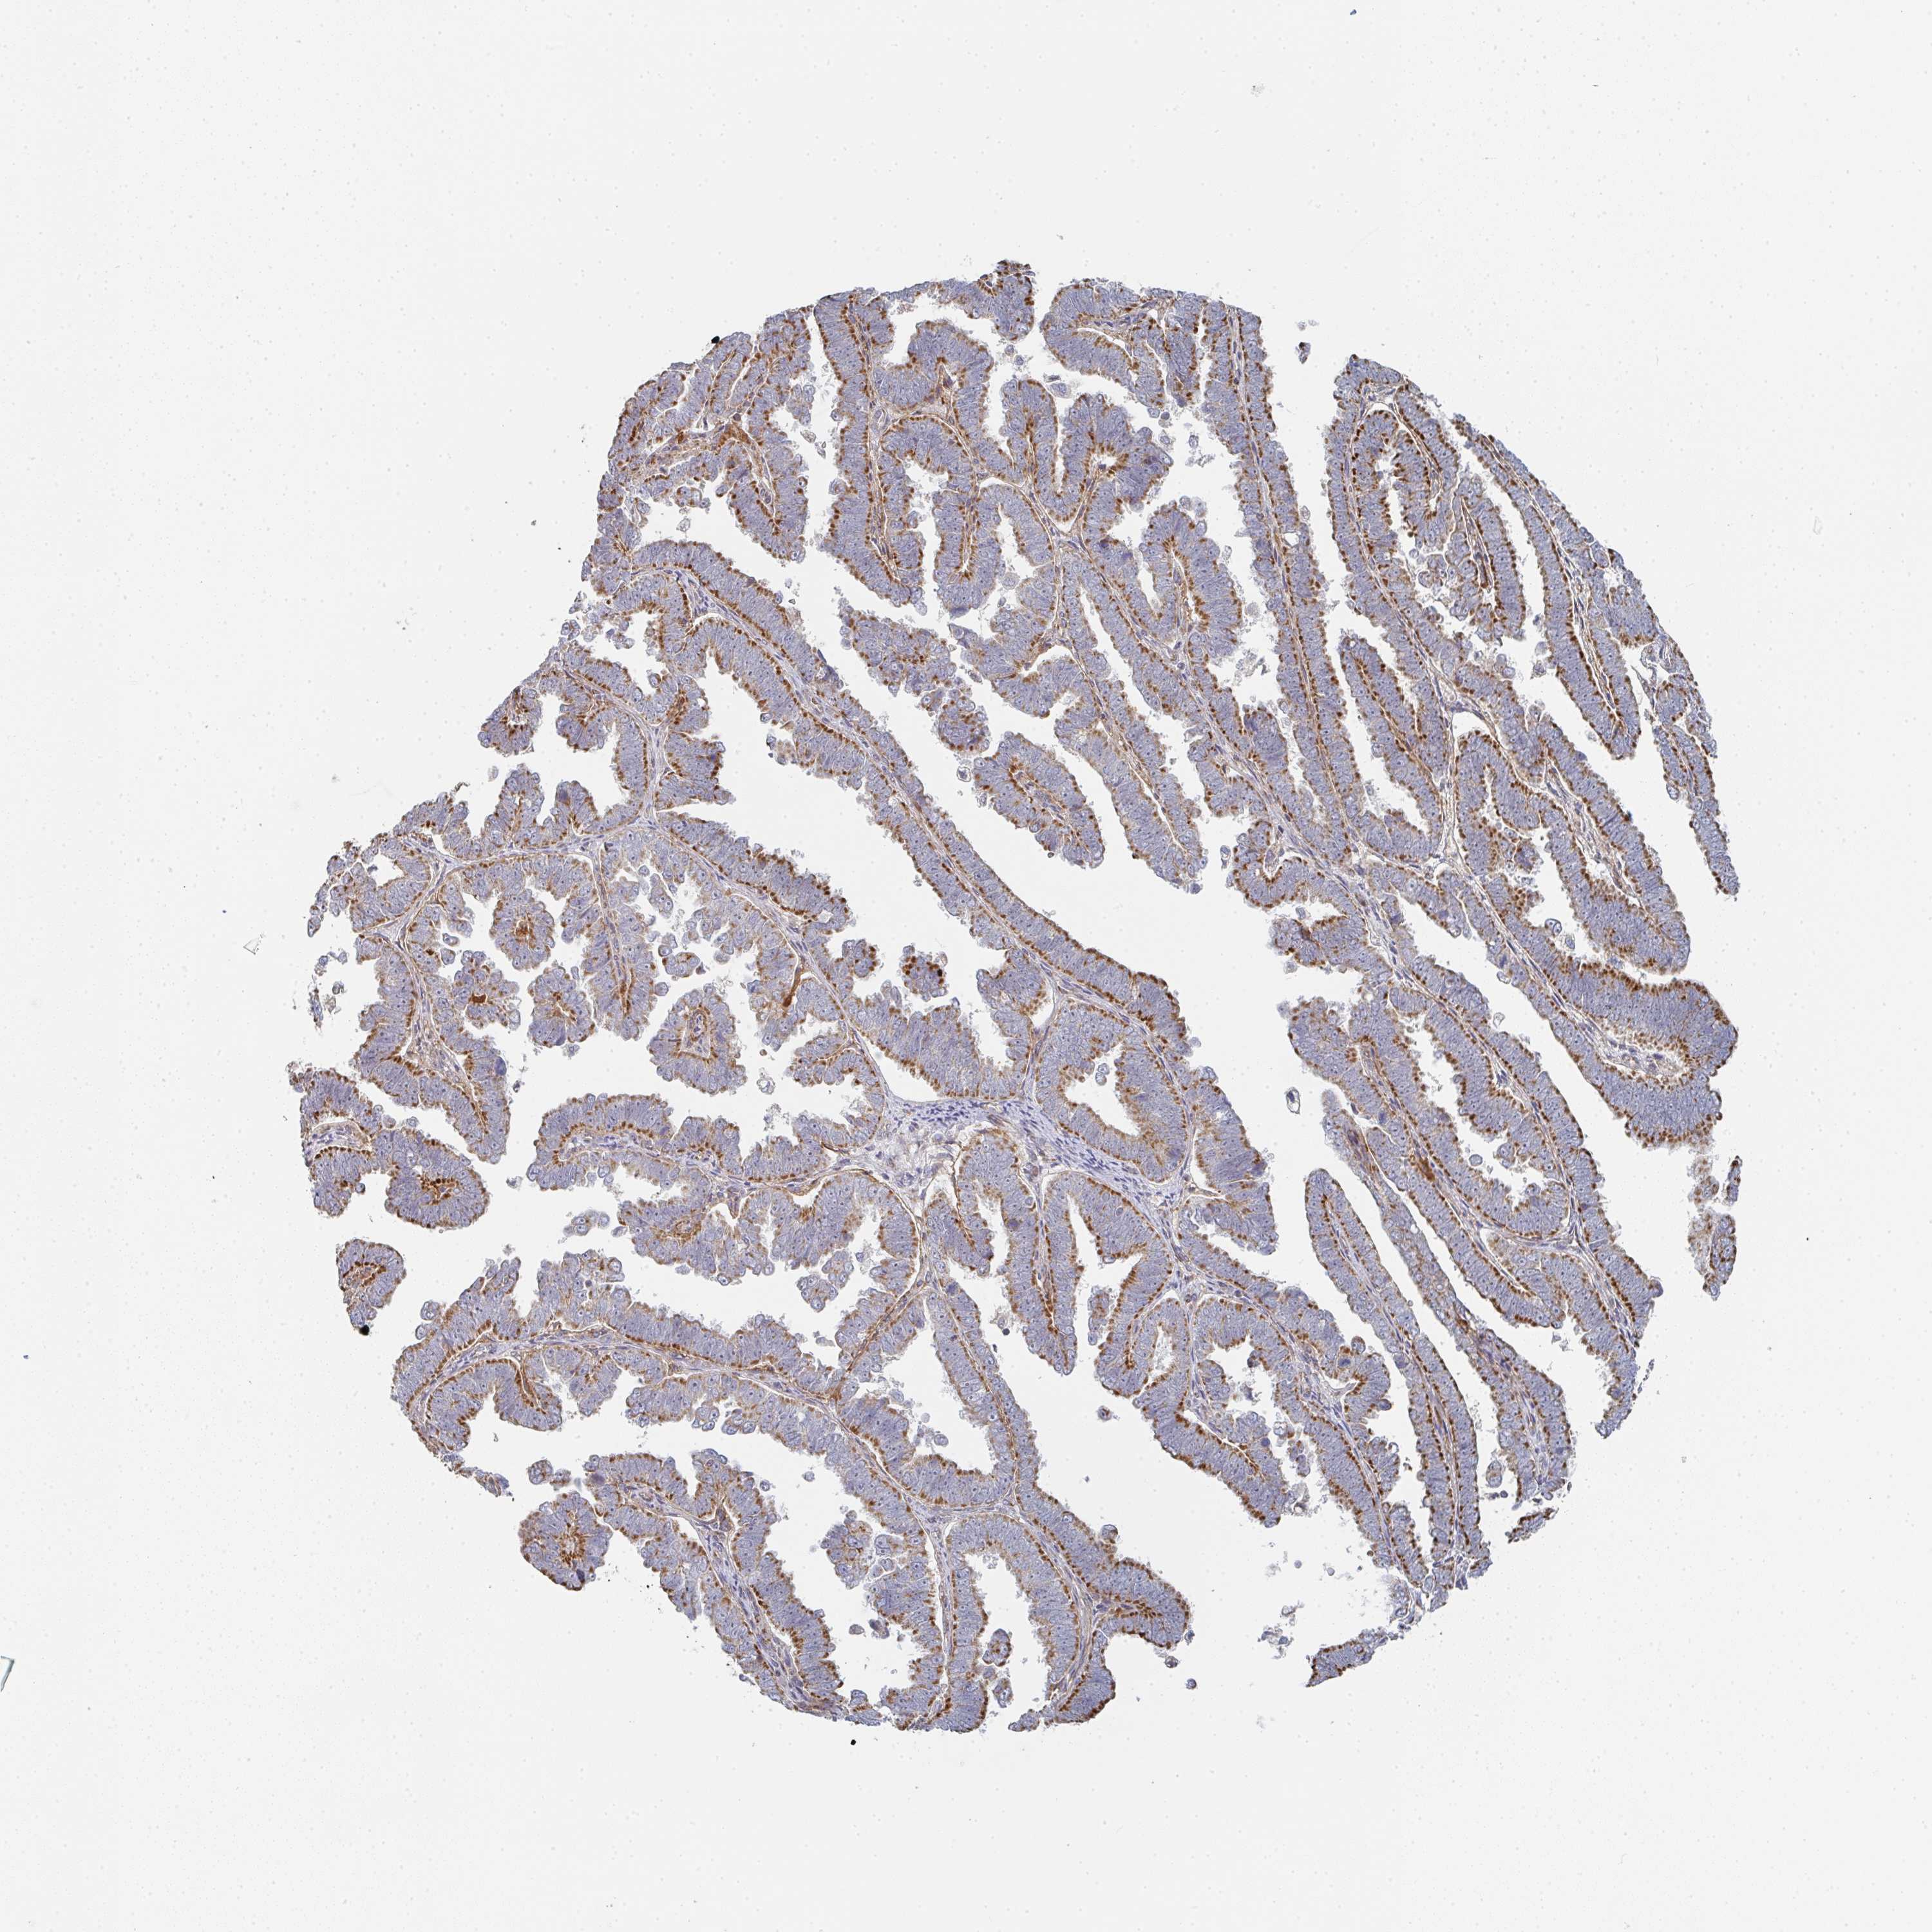

ENDOMETRIAL CANCER - Protein expressioni

A mouse-over function shows sample information and annotation data. Click on an image to view it in a full screen mode. Samples can be filtered based on level of antibody staining by selecting one or several of the following categories: high, medium, low and not detected. The assay and annotation is described here.

Note that samples used for immunohistochemistry by the Human Protein Atlas do not correspond to samples in the TCGA dataset.

Antibody stainingi

Antibody staining in the annotated cell types in the current human tissue is reported as not detected, low, medium, or high, based on conventional immunohistochemistry profiling in selected tissues. This score is based on the combination of the staining intensity and fraction of stained cells.

Each image is clickable and will lead to virtual microscopy that enables deeper exploration of all samples and also displays staining intensity scores, fraction scores and subcellular localization as well as patient and tissue information for each sample.

Antibody HPA023070

Antibody HPA056609

Staining

High

Medium

Low

Not detected

Intensity

Strong

Moderate

Weak

Negative

Quantity

>75%

75%-25%

<25%

None

Location

Nuclear

Cytoplasmic/membranous

Cytoplasmic/membranous,nuclear

Adenocarcinoma, NOS